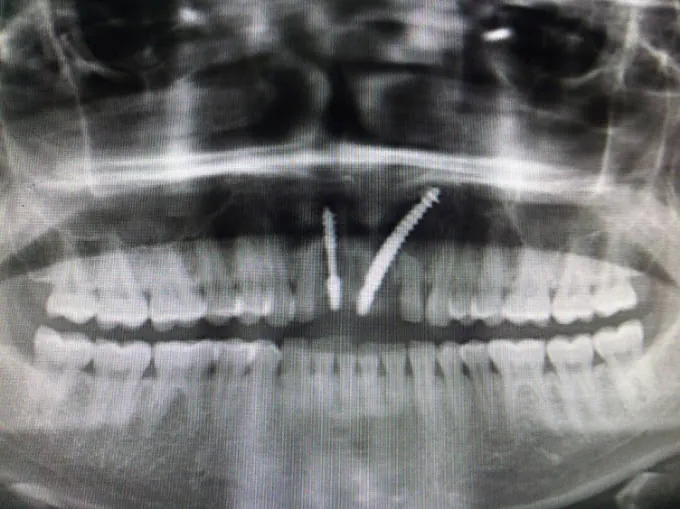

Modern imaging for accuracy

We use digital X-rays for precise diagnostics.